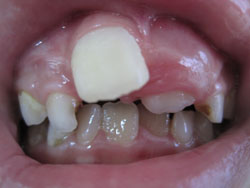

*Hô răng hàm trên, hô hàm trên:

- Hô răng hàm trên và hô hàm trên là một lệch lạc khá phổ biến, làm cho khuôn mặt không thẩm mỹ.

Hô răng hàm trên là tình trạng răng cửa hàm trên trên nghiêng nhiều ra trước, trong khi xương hàm trên vẫn bình thường theo tương quan chiều trước sau.

Hô Hàm trên là tình trạng hàm trên nhô quá về phía trước, hoặc hàm dưới lùi quá về phía sau